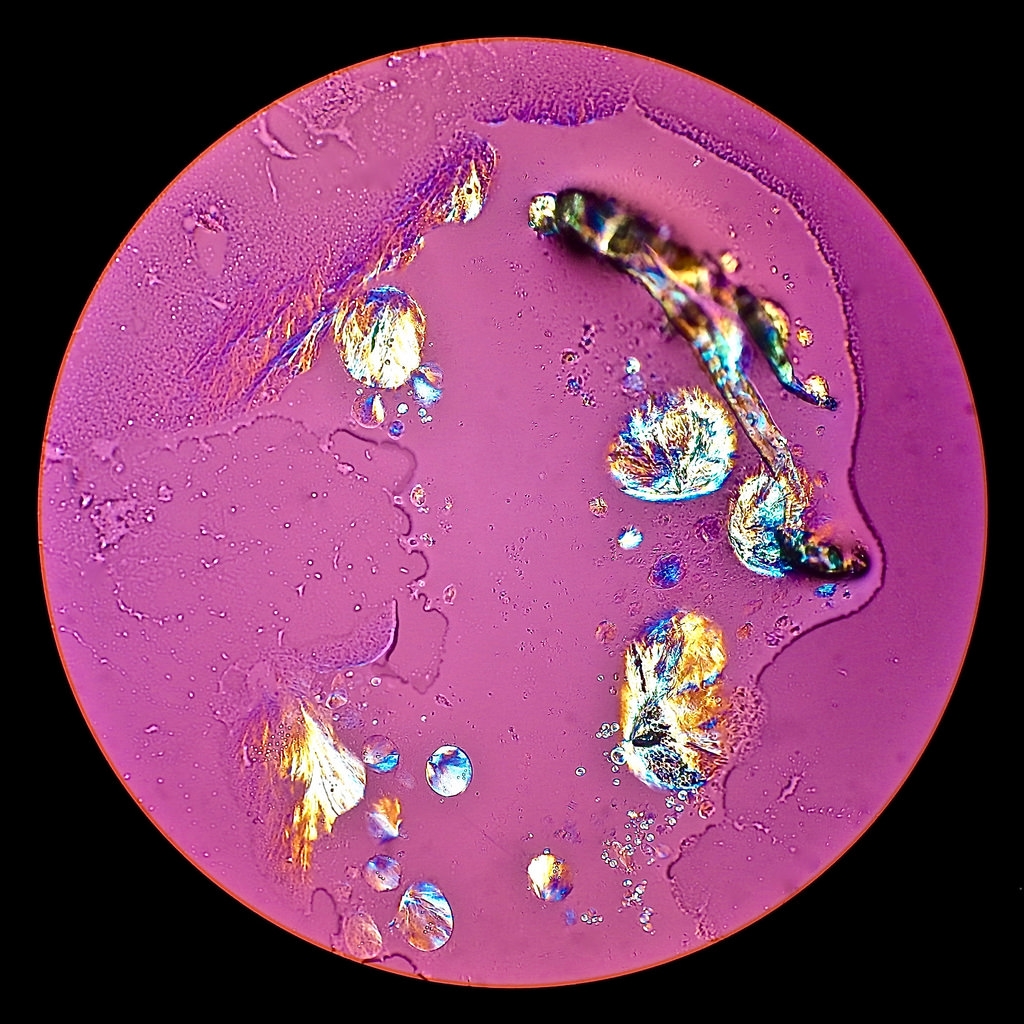

Mikrofotos 1 - 3 :  Schmelzpräparat mit Deckglas nach 2 Stunden Standzeit, das Deckglas ist während des Schmelzvorganges abgesprengt worden ! • Spiegelreflexmikroskopie mit Leitz Auflicht-Interferenz-

kontrast ICR • NPL 10 x / 0.20 P.

Mikrofotos 4 - 10 :  Verdunstungspräparat ohne Deckglas nach 16 Stunden Standzeit • POL + Lambda und ohne Lambda • PL APO 16 / 0.40.